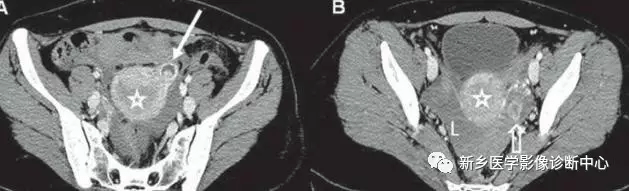

21 异位妊娠

文章图片